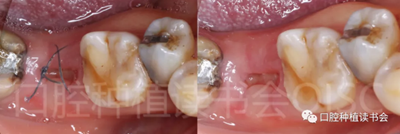

一直以來,即刻種植都是熱點(diǎn)話題,有非常多的研究與臨床觀察聚焦于美學(xué)區(qū)即刻種植,但同時我們在臨床上會發(fā)現(xiàn)許多由于齲壞、隱裂、牙周病及根尖周病無法保留的后牙,患者也渴望獲得即刻種植治療(圖1)。

圖1 無法保留的上頜隱裂后牙,拔牙后即刻種植。